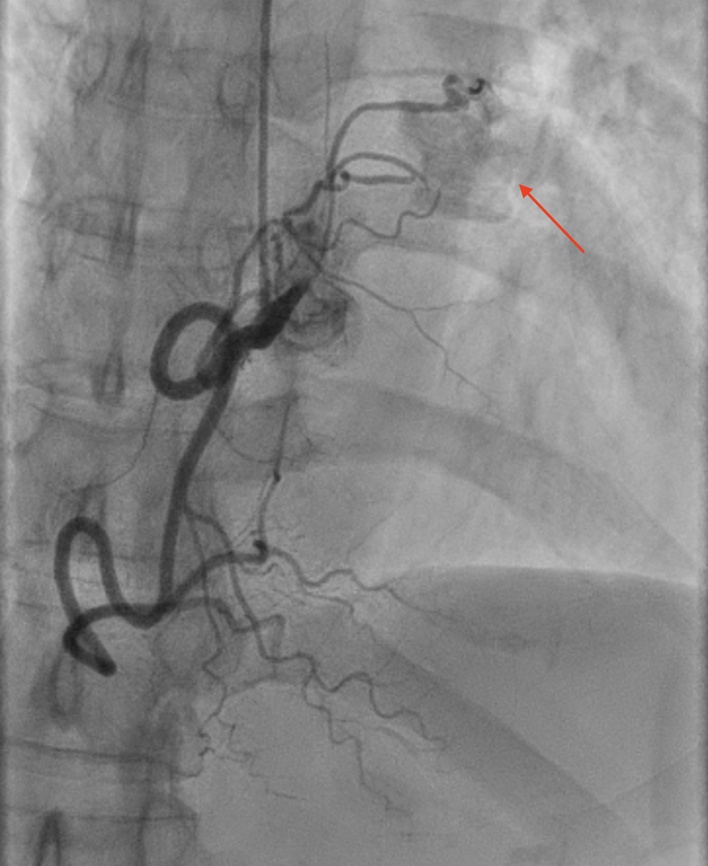

Coronary angiography showed very tortuous coronary arteries with three fistulae from the left anterior descending, left circumflex and right coronary arteries, all terminating in the pulmonary artery (figures 1–3). There was no evidence of obstructive coronary artery disease. Initial presumed diagnosis was myocardial infarction due to coronary steal syndrome. Cardiac magnetic resonance (CMR) imaging was performed. A standard protocol of white blood and cine image sequences with late gadolinium enhancement was used. Shunt assessment via formal volumetric analysis and flow analysis through the valves was performed. True forward stroke volume through the aortic valve was 99 ml/beat with a peak gradient across the valve of 8 mmHg and a regurgitant fraction of 1%. True forward flow through the pulmonary valve was 102 ml/beat. This confirmed that there was no significant shunt. Normal biventricular size and function, with no prior infarction, was also demonstrated. There was a small concentric pericardial effusion with a focal region of inferolateral epicardial fibrosis, suggesting a diagnosis of myopericarditis. The patient was treated with regular colchicine for three months, and ibuprofen, as required. Her troponin and symptoms settled and she was discharged.